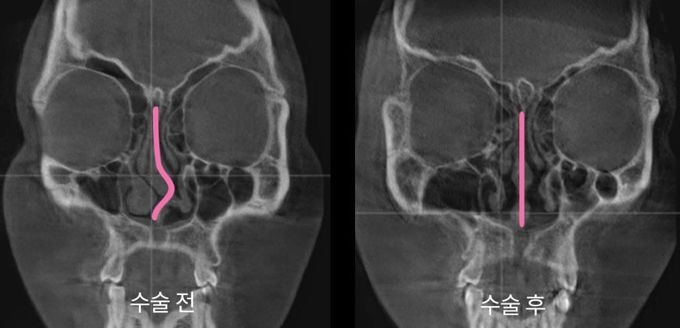

[µ¥Àϸ®¸Þµð ¹Ú´ëÁø ±âÀÚ] ¾ÆÀ̵𺴿øÀÌ ÄÚ»À °ñÀý º¹¿ø ¼ö¼ú Àü¹®¼º °íµµÈ­ µî ÄÚ¼ö¼ú ºÐ¾ß È®Àå¿¡ ³ª¼±´Ù. ´Ù¾çÇÑ ÇùÁø ½Ã½ºÅÛÀ» °®Ãß°í ÀÖ´Â ¸¸Å­ Àü¹®¼ºÀ» Á¦°íÇÑ´Ù´Â º¹¾ÈÀÌ´Ù.

¾ÆÀ̵𺴿øÀº À̺ñÀÎÈİú, ¼ºÇü¿Ü°ú, ¸¶ÃëÅëÁõÀÇÇаú µî Àü¹®ÀÇ ÇùÁø ½Ã½ºÅÛÀ» ÀÌÀü ´ëºñ ¼¼ºÐÇϰí ÄÚÀÇ ±â´ÉÀû ºÎºÐ°ú ½É¹Ì¼º °³¼± µî ´Ù¾çÇÑ ÄÚ °ü·Ã Ä¡·á¸¦ È®´ëÇÑ´Ù.

±× ÀÏȯÀ¸·Î ÄÚ»À °ñÀý º¹¿ø ¼ö¼ú°ú °ü·ÃÇÑ Àü¹®ÀǸ¦ ¿µÀÔÇϰí, ÷´ÜÀåºñ Ȱ¿ë¼º È®´ë µîÀ» ÅëÇØ ¼ö¼ú Àü¹®¼ºÀ» ³ô¿´´Ù.

ÄÚ»À °ñÀýÀº ¸ð¾ç»Ó¸¸ ¾Æ´Ï¶ó ÄÚ¶óÀÎ, ºñÁß°Ý µî ´Ù¾çÇÑ ¹®Á¦¸¦ À¯¹ßÇÑ´Ù. °³Àο¡ µû¶ó Áõ»óµµ »óÀÌÇØ °¢ ¿µ¿ª Àü¹®ÀÇ °£ ÇùÁø Ä¡·á¸¦ ±âº»À¸·Î ÇÑ´Ù.

¾ÆÀ̵𺴿øÀº ÷´Ü 3D-CT¸¦ ÅëÇÑ Á¤È®ÇÑ °Ë»ç¿Í À̺ñÀÎÈİú ¹× ¼ºÇü¿Ü°ú, ¸¶ÃëÅëÁõÀÇÇаú µî Àü¹®ÀÇ ÇùÁøÀ» ÅëÇØ ´çÀÏ ÇÑ ¹ø¿¡ ¸ðµç °úÁ¤À» ¼ö¼úÇÏ´Â ½Ã½ºÅÛÀ» ±¸ÃàÇß´Ù.